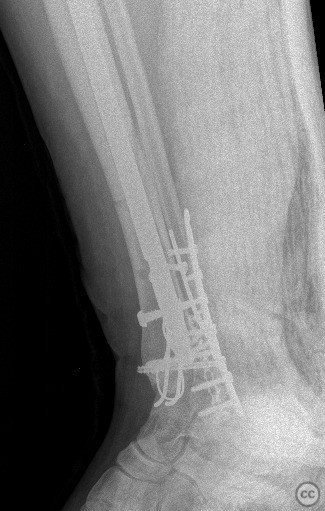

Planning remarks:  The preoperative plan included a staged approach: initial stabilization of the tibial shaft fracture with an intramedullary nail via an infrapatellar approach, followed by open reduction and internal fixation of the trimalleolar ankle fracture through separate medial and posterolateral incisions.

The combination of ipsilateral tibial shaft and trimalleolar ankle fractures presents technical challenges in maintaining alignment and stability during fixation. Sequential fixation allowed for restoration of tibial length and rotation prior to addressing the articular surface of the ankle. Careful soft tissue handling was required due to the proximity of multiple incisions. Stable fixation of all malleolar fragments was achieved with lag screws and neutralization plating as indicated.

Orthopaedic implants used:   tibial intramedullary nail; 3.5mm tubular plate; 4.0mm cannulated screws; mini plate, k wire, cerclage